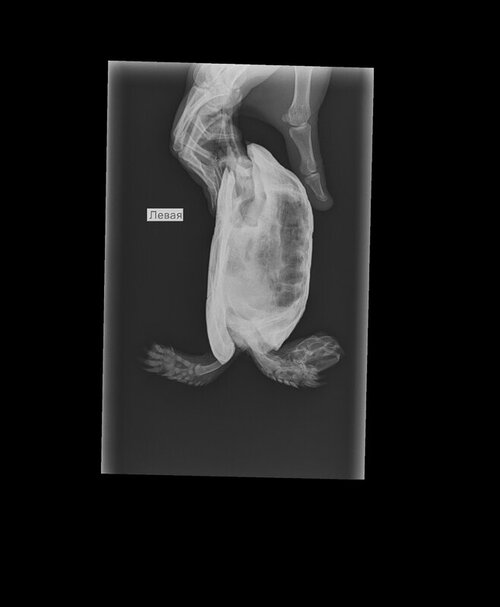

Нашла клинику, где сделают рентген. 3 проекции нужно, верно?

2.jpg

3.jpg

4 (1).jpg

могу предложить консультацию у герпетолога в телеграмм канале, она стоит 300р за весь курс, оплата после консультации. Тут нужно чтобы врач смотрел рентген на наличие воспаления или проблем с жкт.